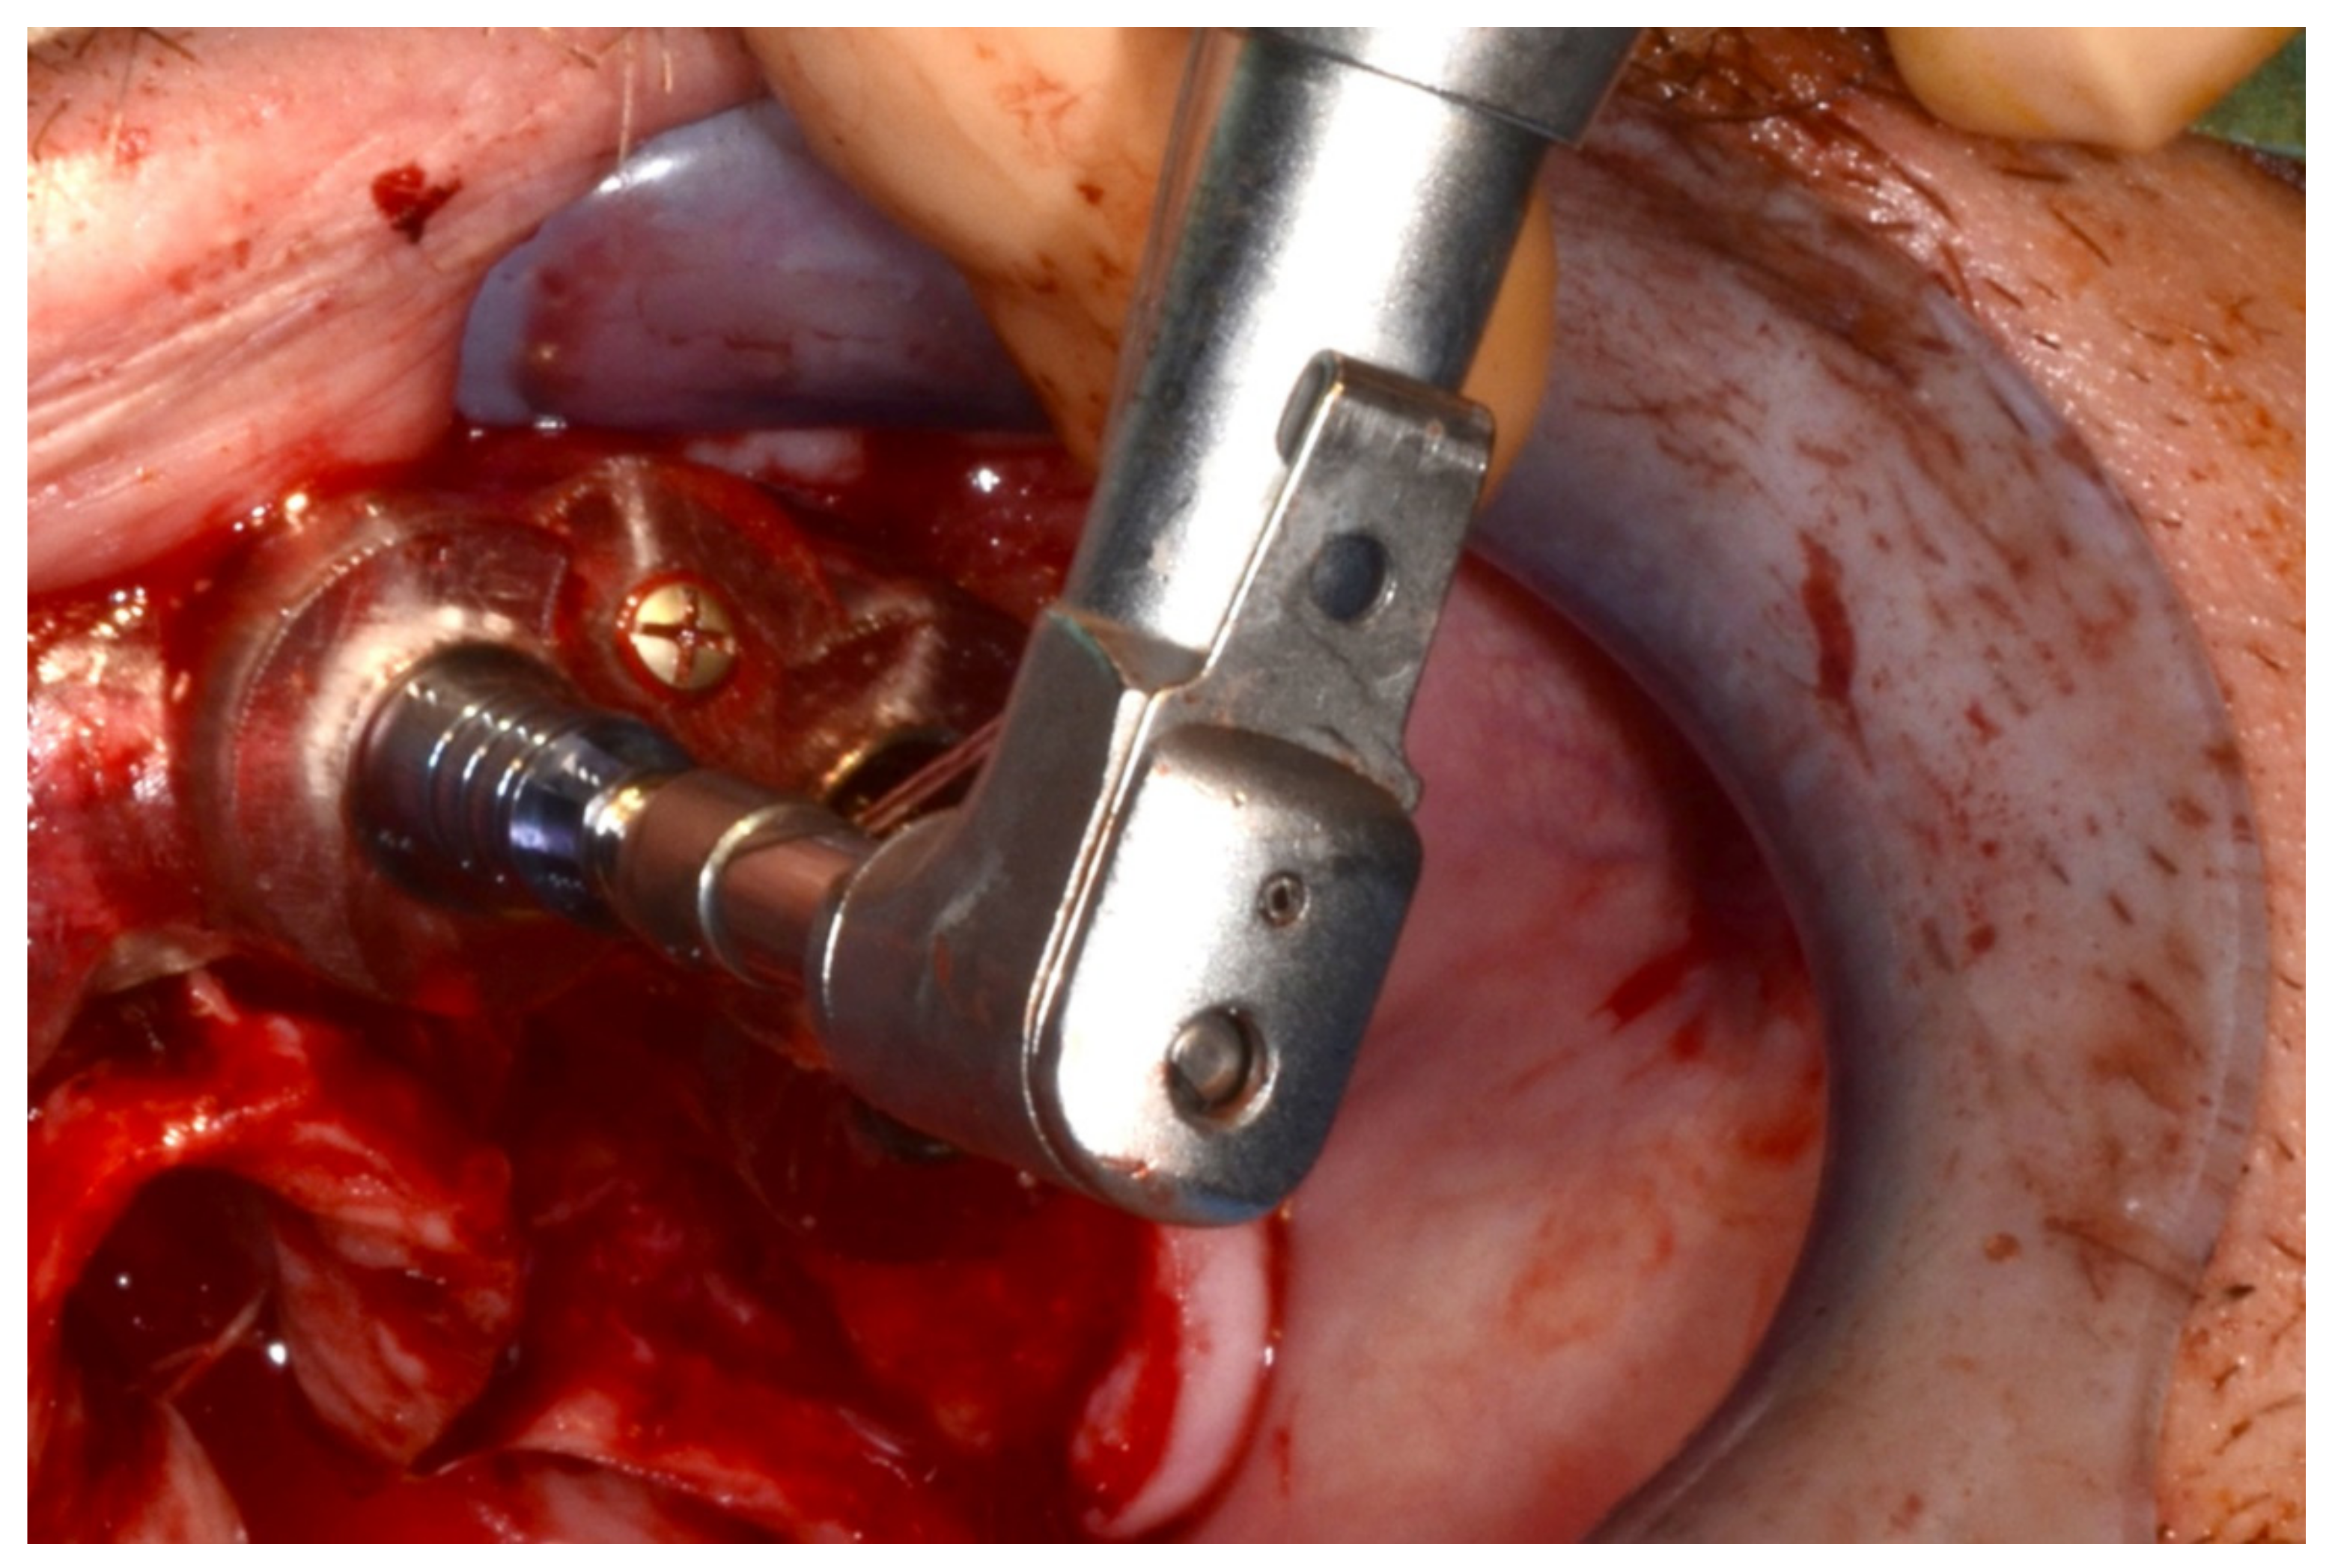

6.2.4. Intra-Operative Documentation:

6.3.4. Intra-Operative Documentation: